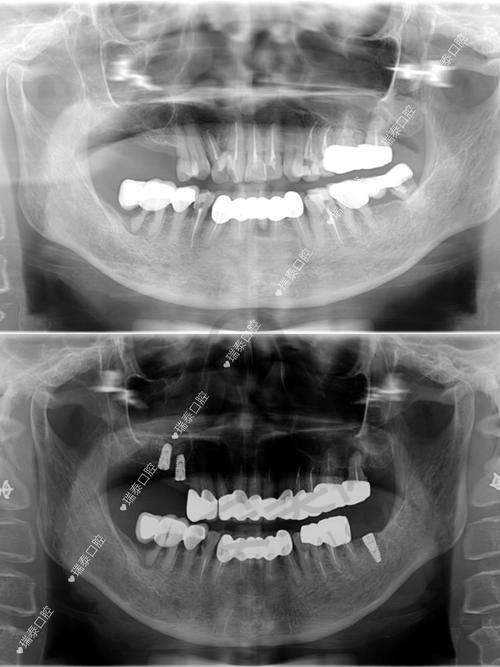

仅仅价格便宜可不行,种牙技术才是关键。汕头天佑口腔中 心在种牙技术方面有着坚实的保护。首先,它拥有一支专精的医疗团队。医生们不仅具备扎实的理论知识,还拥有丰富的临床实践经验。他们能够根据患者的具体情况,制定个性化的治疗方案,确保种植牙的成效和安心性。

其次,医院引进了精良的医疗设备。这些设备不仅能够提高种植牙的精细度,还能减少手术过程中的不适感,提升患者的体验。在手术过程中,医生可以借助精良的设备更正确地操作,大大提高了种植牙的成功几率。

再者,医院注重每一个细节,从术前检查、手术过程到术后护理,都有严格的医疗流程。术前会对患者进行全方面的检查,评估患者的口腔状况和身体状况,确保手术的安心性。手术过程中严格遵循规范操作,术后还会提供完善的护理服务,包括定期复查、口腔卫生指导等,确保种植牙的长期稳定和健康。